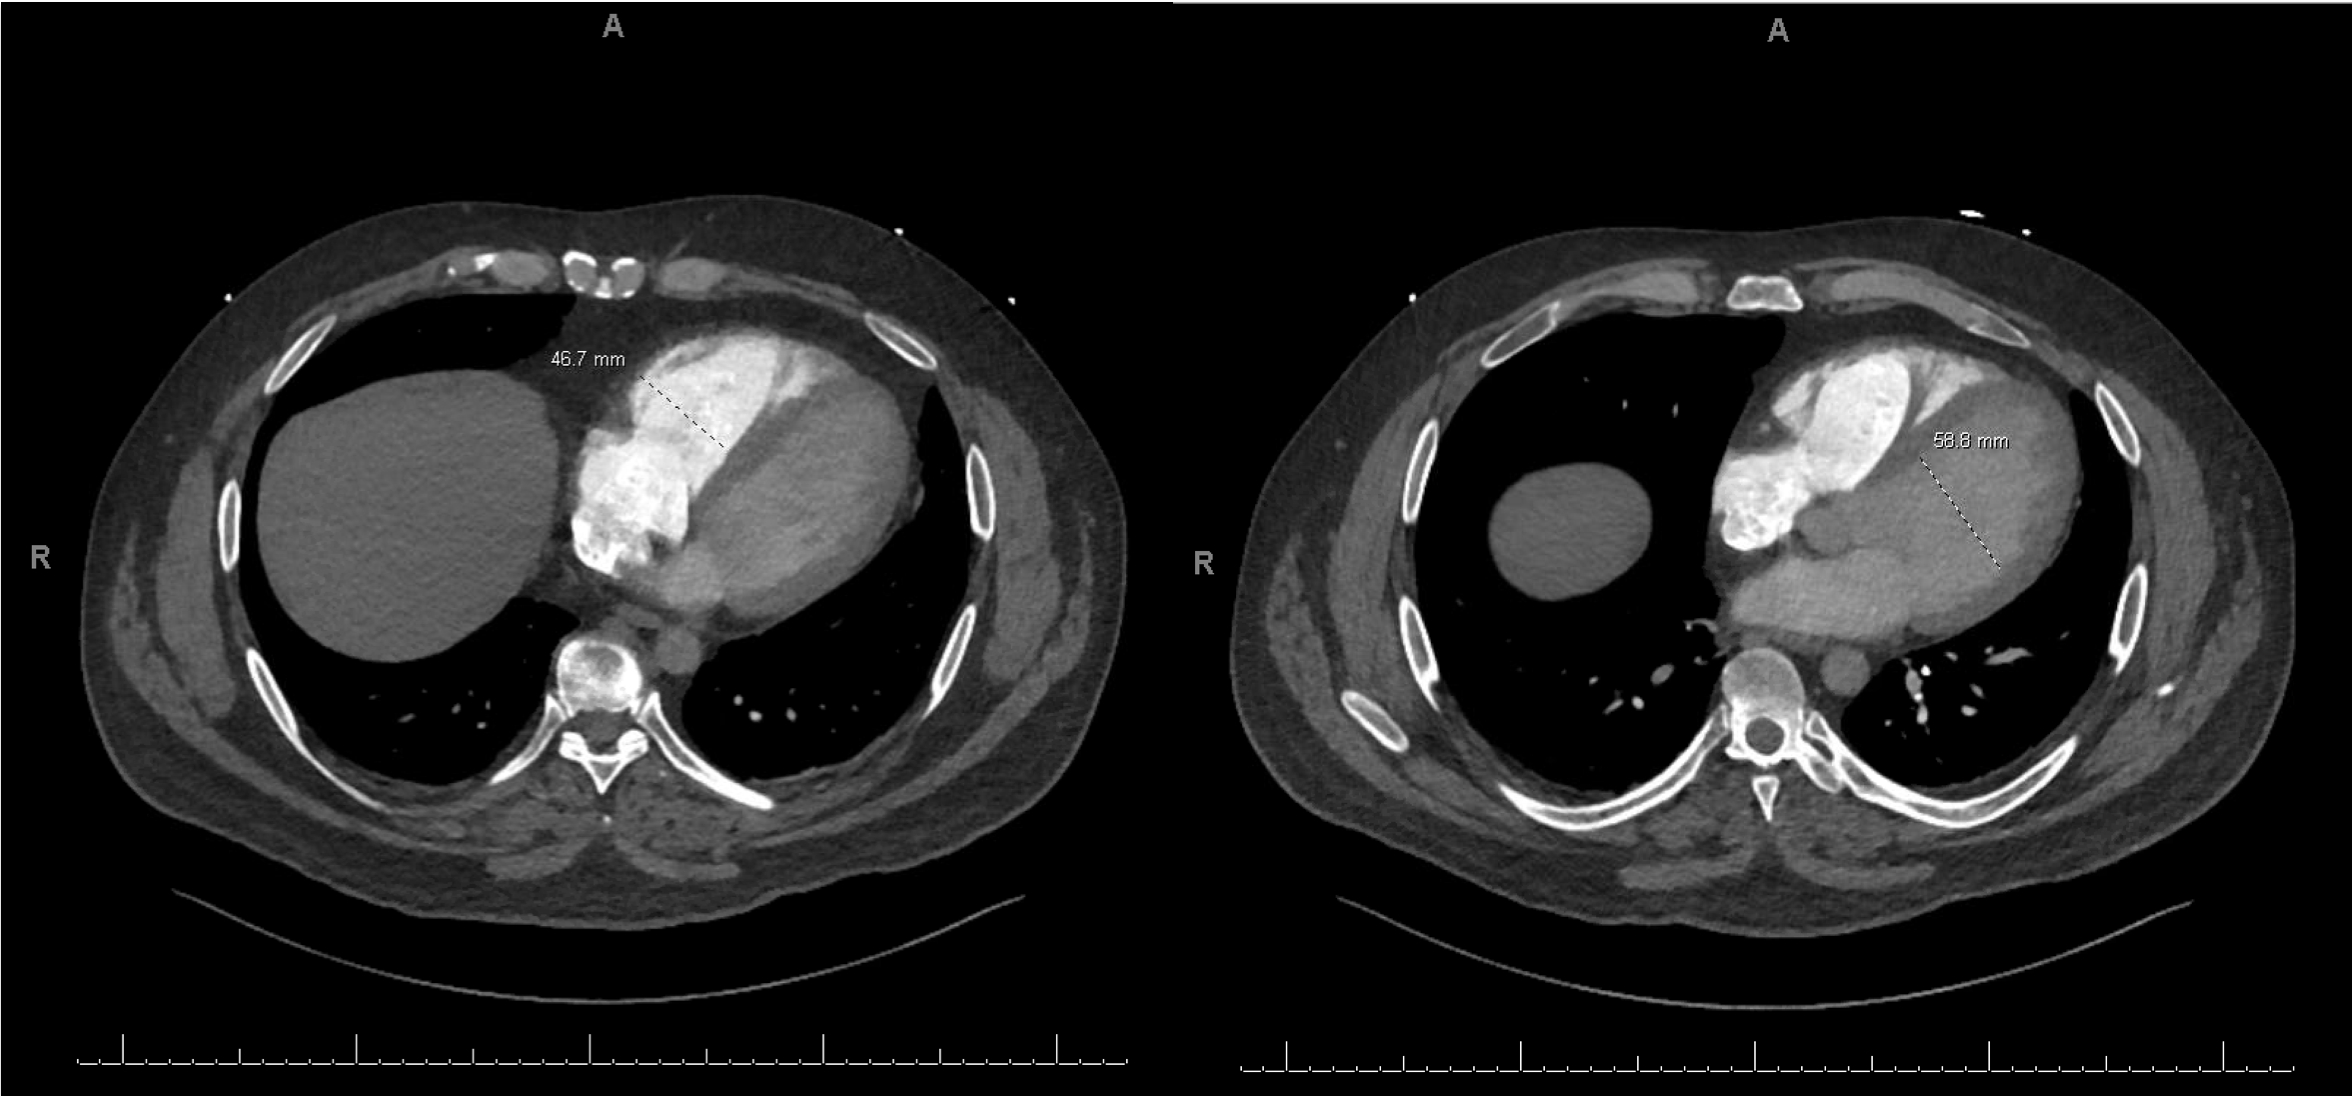

A 44-year-old male with a remote history of resected melanoma presented with acute-onset left upper extremity numbness and discoloration, progressing proximally. He also reported worsening dyspnea over one week. Physical exam revealed an absent left radial pulse and oxygen requirement of 6L via nasal cannula. CT angiography identified a left axillary artery thrombus with distal brachial artery reconstitution and bilateral pulmonary emboli. RV strain was confirmed by an RV/LV ratio of 1.2. Transthoracic echocardiogram demonstrated RV dilation and dysfunction, with a suspected PFO.